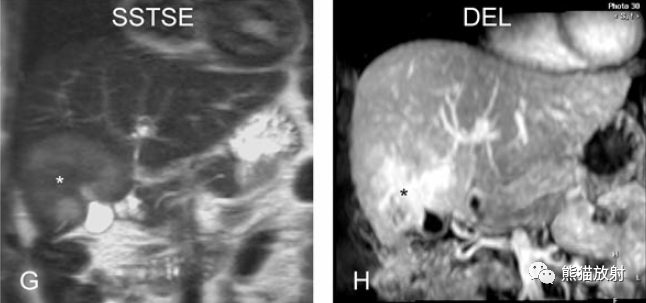

另一例胆囊癌,T2WI及增强延迟期显示胆囊壁不均匀增厚并明显强化。

胆囊癌。病灶以胆囊为中心侵及肝脏,明显弥散受限,由于病灶内含结缔组织/纤维成分(T2低信号)导致肝被膜内陷,增强扫描动脉期明显不均质强化,延迟期中心纤维成分延迟强化。表现类似肝内胆管细胞癌。

胆囊壁增厚(并肝硬化、门脉高压、腹水)。T2WI显示胆囊壁因水肿而光滑均匀增厚,增强延迟期显示强化的胆囊壁(内外两层:粘膜层和浆膜层),薄而清晰光滑。